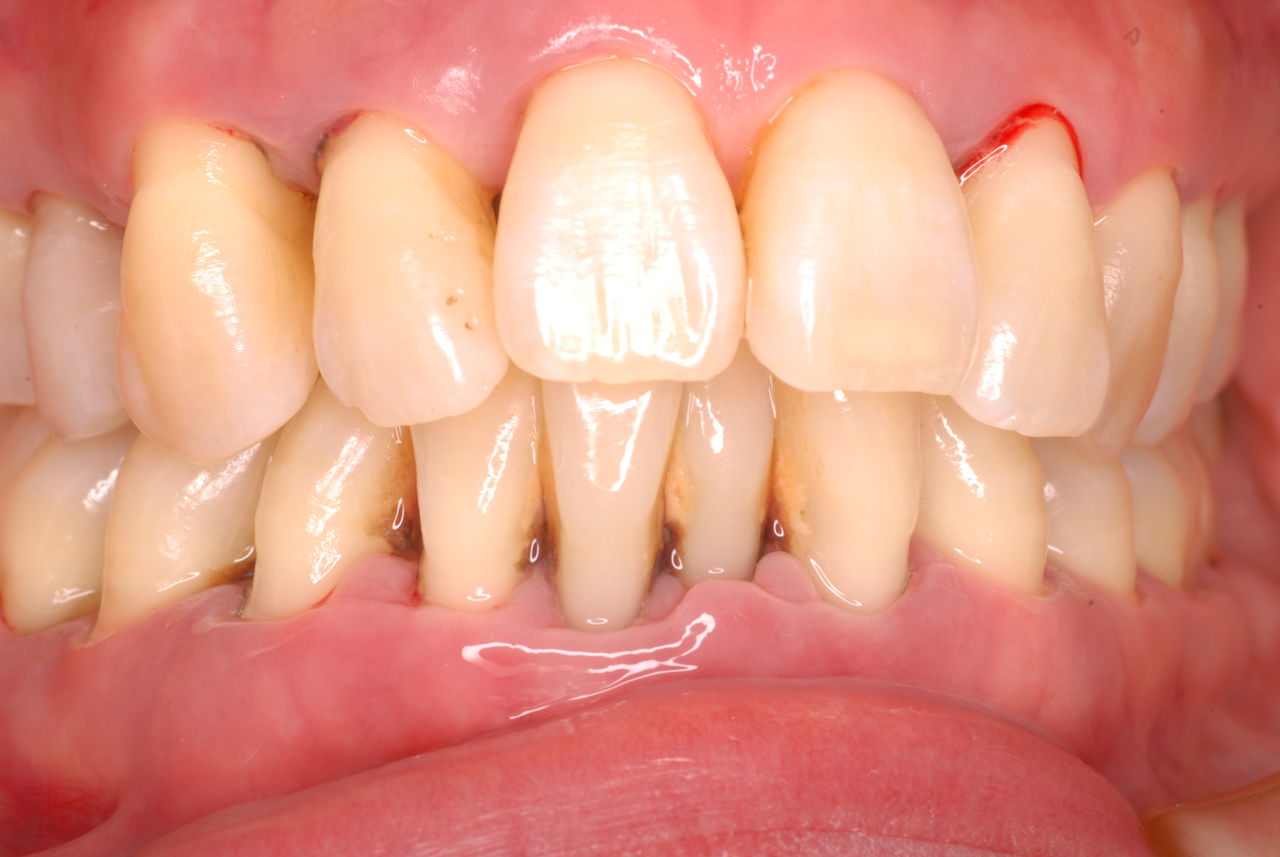

ある方の例です。親不知が痛くなってきました。一見問題ないようです。でも歯周病を常に治療している優れた歯科医師ならば、乾燥させてみた歯茎の色の変化で殆ど歯周病罹患部を指摘できるそうです。

検査をすれば恐ろしいほどの状態だといえるのです。10年後は虫歯と歯周病で残っている歯は何本なのか心配になってきました。

初診から数週間後大分よくなったとはいえまだまだ簡単な検査でも血だらけなのですね。